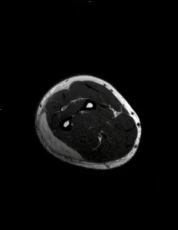

En el tejido celular subcutáneo del codo, tercio proximal y medio del antebrazo existe una colección superficial a la musculatura que tiene intensidad de señal heterogénea por zonas de menor intensidad de señal hacia la periferia, tiene medidas aproximadas de 19 x 5.4 x 1.2 cm con un volumen aproximado de 64.39 cm³.